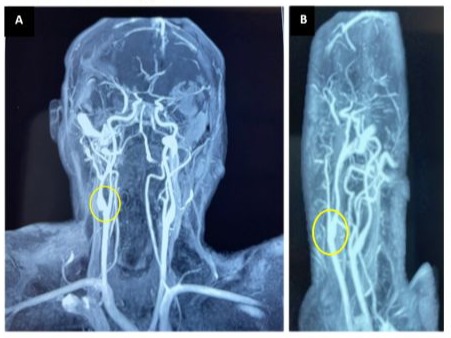

A comprehensive etiological workup for ischemic stroke in a young adult—including ECG, transthoracic and transesophageal echocardiography, cervical-transcranial ultrasound, serologic tests, and inflammatory markers—was entirely negative. Cerebral MRI with arterial angiography revealed a thin, linear filling defect along the posterior-lateral wall of the right carotid bulb, consistent with a right carotid web, which was identified as the likely cause of the infarct (Figure 1).

Figure 1: Cerebral MR angiography: Sagittal view (A) and coronal view (B) showing a right carotid web, appearing as a linear filling defect along the posterior-lateral wall of the right carotid bulb.